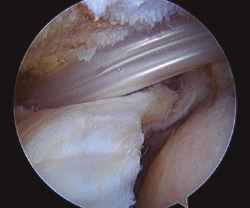

El ascenso de la cabeza humeral durante la contracción del deltoides es el origen biomecánico de la disfunción del hombro y de la degeneración articular cuando se produce una rotura masiva del manguito. Para combatir este fenómeno se desarrolló la técnica del espaciador subacromial biodegradable, cuyo objetivo es mantener la cabeza centrada durante la contracción del deltoides(12)(Figura 1). Sin embargo, la experiencia derivada de su uso es todavía limitada, sin que se hayan definido con exactitud los resultados ni las complicaciones a medio o largo plazo.

Figura 1. Implantación del espaciador subacromial previa a su relleno con suero salino.